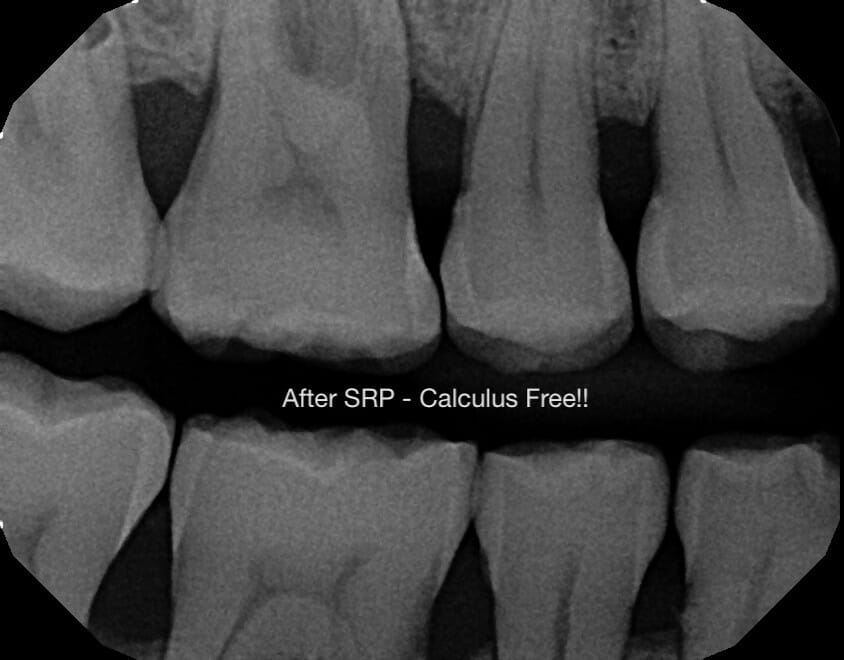

![]()

One of our two awesome hygienists (Ciera or Edith) will remove the bacteria from underneath your gums. Once this is done, your gums will have a higher likelihood of shrinking back to a healthier, more stable, state.

This will also help to reduce or eliminate the bleeding you experience while brushing, while at the same time improving your overall gum tissue health – which will ultimately help to keep all of your current teeth present and in the correct place.

Following our assessment, we’ll use a few injections of anesthetic to numb your teeth and gums. Then we will use our water pressure tool to clean out the bacteria before doing our final assessment, and maybe taking some additional X-rays to make sure we’ve removed all of the bacteria.

Because the bacteria have built up over (in many cases) years below your gums, once that bacteria is gone, it’s common to feel like you have holes between your teeth or even cavities in them. Don’t worry – that’s not the case!

What’s true is that so much bacteria has been removed so that your gums can shrink back to a healthy size. Although the feeling is a “weird” one – it’s a great sign that you’ve just made tremendous progress.